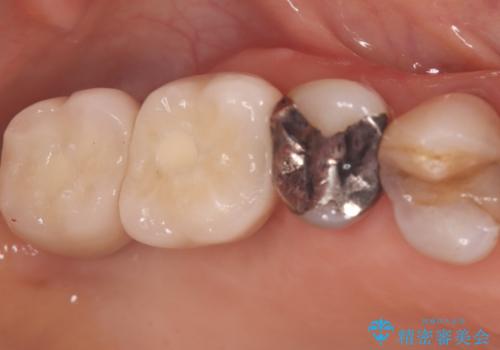

その後、インプラントと骨がしっかりと結合するのを待ってから、最終的な被せ物(クラウン)を装着。これにより、重度歯周病で失われた2本の奥歯を、強固で安定したインプラントで再建。以前のような不安なく、しっかりと噛める快適な食生活を取り戻していただけました。